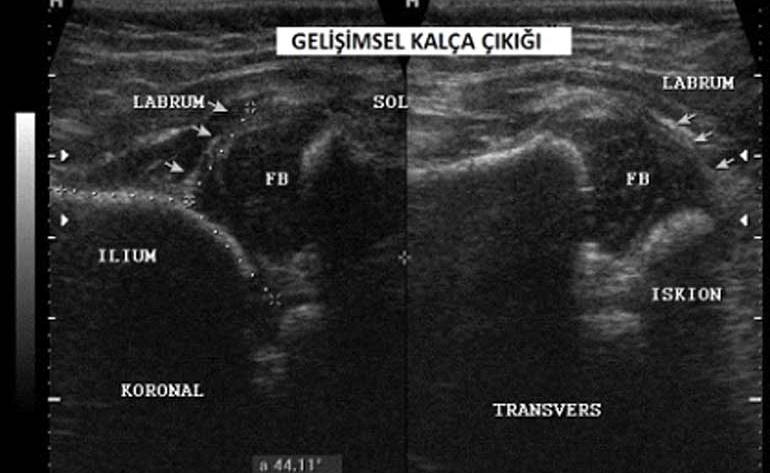

نحن نسمي هذا المرض خلع الورك الخلقي . لا يمكن إجراء التشخيص النهائي إلا عن طريق تصوير الورك. إذا تم تشخيصه في أول 3-4 أشهر ، فأن العلاج يحقق النتيجة المرجوة.

لقد عملت بمجال التصوير منذ 25 عامًا . وانا انصح إذا كان هناك مرض الخلع الولادي في الأسرة ، يجب تطبيق الموجات فوق الصوتية في…